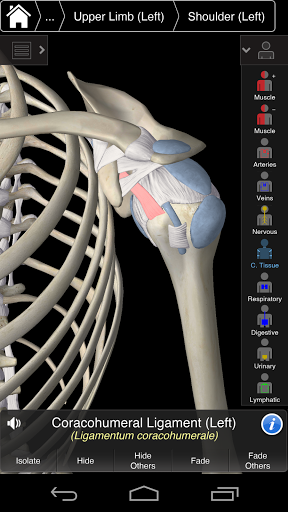

Essential Anatomy 3 représente la toute dernière technologie 3D révolutionnaire et un design innovant. Un moteur graphique 3D de pointe, construit sur mesure par 3D4Medical à partir de zéro, alimente un modèle anatomique très détaillé et fournit des graphiques de qualité exceptionnelle qu'aucun autre concurrent ne peut atteindre.

L'application représente une approche unique à l'apprentissage de l'anatomie générale. Les graphismes sont inégalés et rendent l'apprentissage, grâce à l'utilisation de contenu informatif et de fonctionnalités innovantes, une expérience riche et engageante.

Essential Anatomy 3 est réactif, visuellement magnifique et sans effort. L'application est entièrement 3D, ce qui signifie que vous pouvez voir n'importe quelle structure anatomique dans l'isolement, ainsi que de n'importe quel angle.

La fonctionnalité intelligente trouvée dans l'application permet à l'utilisateur de dépouiller les couches de muscle via l'outil «scalpel». Cette application offre aux utilisateurs la possibilité d'activer / désactiver des systèmes sans avoir à désélectionner des structures individuelles ou à se frayer un chemin à travers une multitude d'onglets régionaux prédéfinis, comme d'autres applications.

Essential Anatomy 3 est conçu en pensant à l'utilisateur - le corps lui-même devient l'interface. Contrairement à d'autres applications 3D, qui reposent sur des arrangements anatomiques prédéfinis et des dissections régionales pour guider l'utilisateur, l'Anatomie 3 essentielle de 3D4Medical vous permet de trouver ce que vous recherchez sans complication.

---- Plus de 4000 structures anatomiques très détaillées

---- Nomenclature latine pour chaque structure anatomique